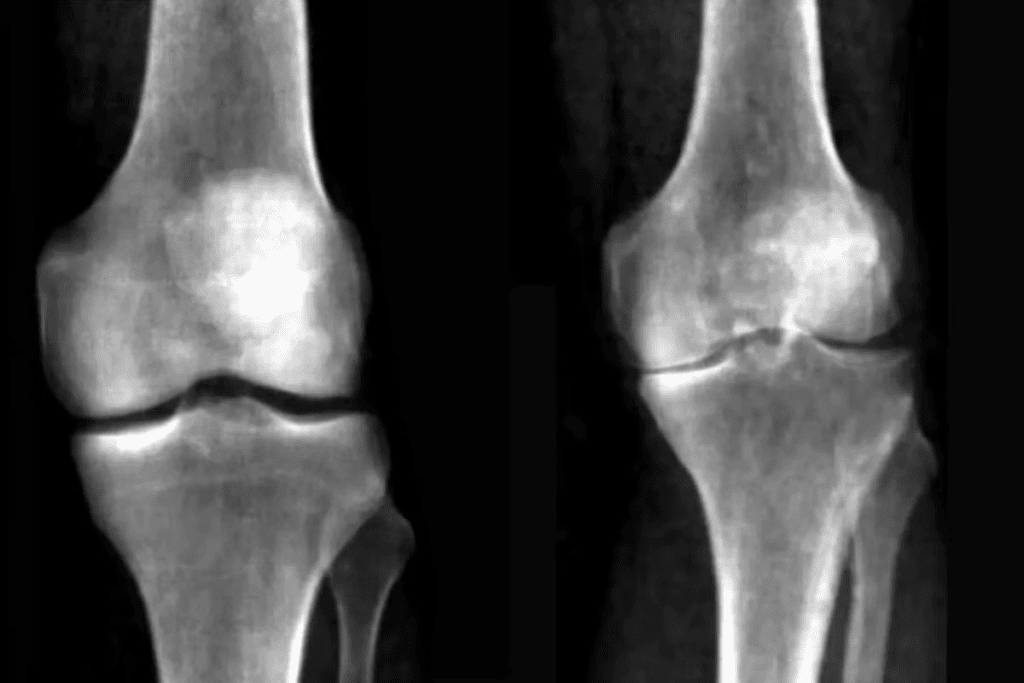

Understanding osteoarthritis is key to tackling knee pain. It’s a degenerative joint disease that damages cartilage, causing pain and stiffness. It’s a common cause of knee pain, mainly in older adults.

Knee osteoarthritis happens when cartilage wears down, leading to bone-on-bone contact. This causes pain, swelling, and less mobility. Factors like age, obesity, and injuries can trigger it.

Imaging tests are key in finding out what’s wrong with your knee. They show us the inside of the knee in detail.

| X-rays | Bone fractures, osteoarthritis | Quick, widely available |